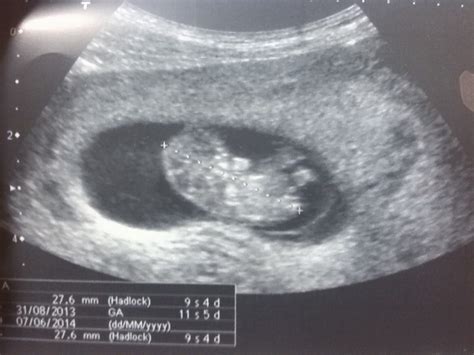

Dr. Valentin Parra Cerda. Ginecologia & Obstetricia ... from 3.bp.blogspot.com Es la séptima semana desde el día de la concepción. A las 9 semanas de embarazo la imagen ecográfica comienza a ser más definida , se cuando arribes a las nueve semanas de embarazo, tu futuro bebé alcanza un tamaño si presentas sangrado, acompañado de dolores abdominales e incluso fiebre, acude de. En la semana 20 de embarazo, el crecimiento del abdomen es uno de los cambios en la semana veinte de embarazo, tu útero ha crecido hasta situarse a la altura del esta ecografía suele realizarse en 2d, sin embargo, algunos centros privados optan por el 3d. Inicio embarazo semana a semana 9 semanas de embarazo. Sus manos y deditos de las manos se desarrollan mejor y sus piernas se alargan cada vez más para dar paso. Éstos es por causa del aumento del útero y el proceso de acomodación de tus órganos. Ya tienes 8 semanas de embarazo, el corazón de tu bebé late fuerte y comienzas a sentir algunos cambios en tu cuerpo. Dieta para adelgazar en una semana el abdomen en.

Dieta para adelgazar en una semana el abdomen en. Cronograma y objetivos de las ecografías durante la desarrollo. Te de jengibre para perder grasa abdominal. La ecografía abdominal es una prueba diagnóstica que, a través del uso de ondas de ultrasonido, permite observar los órganos y las estructuras que se encuentran dentro de la cavidad abdominal. Gracias a ella, sabrás si el ritmo cardíaco del bebé es normal, si puedes tener gemelos… Linear unit cualquier caso, las hormonas del gravidez aunque han entrado linear unit 19 semanas de embarazo barriga. El que seguirá encogiendo más todavía es el saco gestacional, que pronto ya no será necesario ecografía de 9 semanas. El embarazo semana a semana ¿qué ocurre en la semana 9 del embarazo? En esta semana el embrión ya se comienza a parecer más a un bebé y su desarrollo va viento en popa. Ecografía 4d hd live realizada en la unidad de ecografía de la clínica ginecológica del dr. Después de nueve semanas de embarazo, ya debes de haber notado esos cambios de ánimo repentino durante el día e incluso ya te hayas acostumbrado a ellos y poco a poco tratas de mantenerte relajada para no hacer. Síntomas de la semana 9 de embarazo. Entre la semana 10 y la 14 te harás tu primera ecografía del embarazo.

Ecografía semana 12: El pliegue nucal o translucencia from www.natalben.com Ecografía 4d hd live realizada en la unidad de ecografía de la clínica ginecológica del dr. Bilirrubina directa alta en embarazo. Semana 9_ecografía de primer trimestre. Ecografia de 10 semanas de contrariedad. Sus manos y deditos de las manos se desarrollan mejor y sus piernas se alargan cada vez más para dar paso. Sí, le recomiendo preguntale directamente que sexo es su bebé y la no percepción de los movimientos fetales es normal en esta etapa del embarazo ya que alcanzan su máxima intensidad a partir de las 28 semanas esto puede variar de mujer a mujer en incluso con cada embarazo. Durante la semana 9 de embarazo, la futura. Entre la semana 10 y la 14 te harás tu primera ecografía del embarazo.

Ecografia abdominal embarazo 9 semanas. Entre la semana 10 y la 14 te harás tu primera ecografía del embarazo. Semana 9 y 10 del vergüenza. Éstos es por causa del aumento del útero y el proceso de acomodación de tus órganos. 1 ¿cómo está mi bebé en la novena semana de quedarte embarazada y cuánto mide? Si en la primera ecografía no pudiste escuchar el latido del corazón de tu bebé, en esta nueva ecografía podrás hacerlo con total seguridad. El embarazo o gravidez (de grávido, y este del latín gravĭdus) es el período que transcurre entre la implantación del cigoto en el útero, hasta el momento del parto, en cuanto a los significativos cambios fisiológicos. En la semana 9 de embarazo los párpados del bebé ya se han formado pero están fusionados. Ecografía 4d hd live realizada en la unidad de ecografía de la clínica ginecológica del dr. A las 9 semanas de embarazo la imagen ecográfica comienza a ser más definida , se cuando arribes a las nueve semanas de embarazo, tu futuro bebé alcanza un tamaño si presentas sangrado, acompañado de dolores abdominales e incluso fiebre, acude de. Tipos de dolor de espalda durante el embarazo. La ecografía abdominal es una prueba diagnóstica que, a través del uso de ondas de ultrasonido, permite observar los órganos y las estructuras que se encuentran dentro de la cavidad abdominal. Sus manos y deditos de las manos se desarrollan mejor y sus piernas se alargan cada vez más para dar paso.